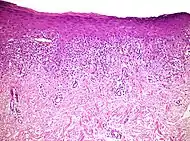

Interface dermatitis with lichenoid inflammation

| Main conditions[2] | Characteristics | Micrograph | Photograph |

|---|---|---|---|

| Generally/Not otherwise specified | Typical findings:[2]

|

||

| Lichen planus | Irregular epidermal hyperplasia with a jagged “sawtooth” appearance, compact hyperkeratosis or orthokeratosis, foci of wedge-shaped hypergranulosis, basilar vacuolar degeneration, slight spongiosis in the spinous layer, and squamatization. The dermal papillae between the elongated rete ridges are frequently dome shaped. Necrotic keratinocytes can be observed in the basal layer of the epidermis and at the dermal-epidermal junction. Eosinophilic remnants of anucleate apoptotic basal cells may also be found in the dermis and are referred to as “colloid or civatte bodies”. Whickham striae are usually seen in the areas of hypergranulosis. Vacuolar degeneration at the basal layer may be noted leading to focal subepidermal clefts (Max Joseph spaces). Squamatization occurs as a result of maturation and flattening of cells in the basal layer. It happens in areas of marked hypergranulosis with prominence of the sawtooth pattern of rete ridges. Wedge-shaped hypergranulosis can occur in the eccrine ducts (acrosyringia) or hair follicles (acrotrichia). In the hypertrophic subtype, the associated hyperkeratosis, parakeratosis, hypergranulosis, papillomatosis, acanthosis, and hyperplasia markedly increased with thicker collagen bundles forming in the dermis. Moreover, the rete ridges are more elongated and rounded as opposed to the typical sawtooth pattern. In atrophic LP, loss of the rete ridges and dermal fibrosis is prominent. In vesiculobullous LP, the disease progression is quicker. Hence, some of the distinctive features such as hyperkeratosis, hypergranulosis, or dense lymphocytic dermal-epidermal infiltrate may not be present. LP lesion may resolve with residual hyperpigmentation caused by a persistent increase in the number of melanophages in the papillary dermis.[9] |  |  |